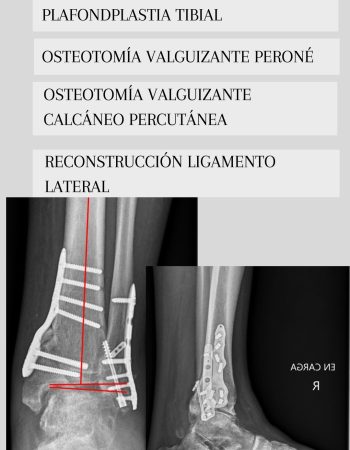

Dada su edad y la existencia de una artrosdesis en el tobillo contralateral decidimos una cirugía de preservación articular mediante plafondplastia de apertura medial. Se asoció osteotomía valguizante de peroné, osteotomía calcánea percutánea valguizante y reconstrucción de ligamento lateral del tobillo mediante aloinjerto como recomiendan las últimas publicaciones en la literatura en casos similares.

Como podéis ver en las imágenes se consiguió mejorar el eje del talón trasladando el eje de carga de al extremidad hacia la zona del tobillo más sana. A pesar de no corregir del todo el tilt talar el paciente se encuentra asintomático.